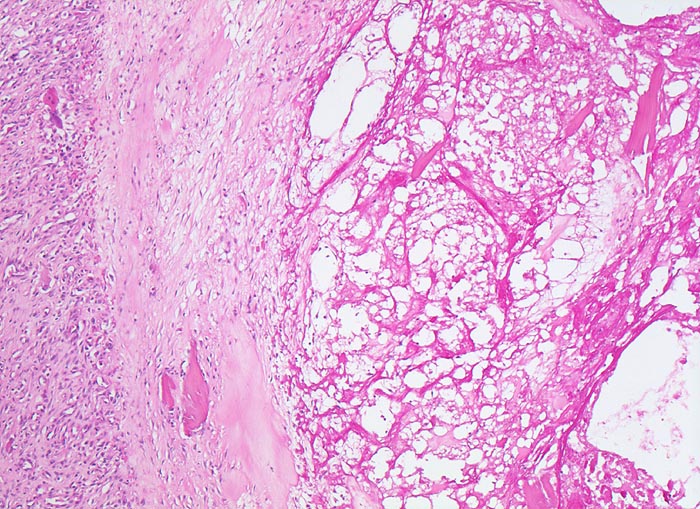

Coxarthrose: Geröllzyste

Knochen, Femurkopf

Randbereich einer Geröllzyste. Im Zentrum der Zyste nekrotischer Detritus mit avitalen Knochenfragmenten. Die Geröllzyste wird umgeben von einem Saum Narbengewebe und daran anschliessend gefässreichem Granulationsgewebe.

74-jährige leicht adipöse Patientin mit Anlaufschmerz, belastungsabhängigem Schmerz und zunehmender Versteifung im Hüftgelenk. Im Röntgenbild des Hüftgelenks zeigen sich eine Gelenkspaltverschmälerung, subchondrale Osteolysen, Usuren und randständige Osteophyten.